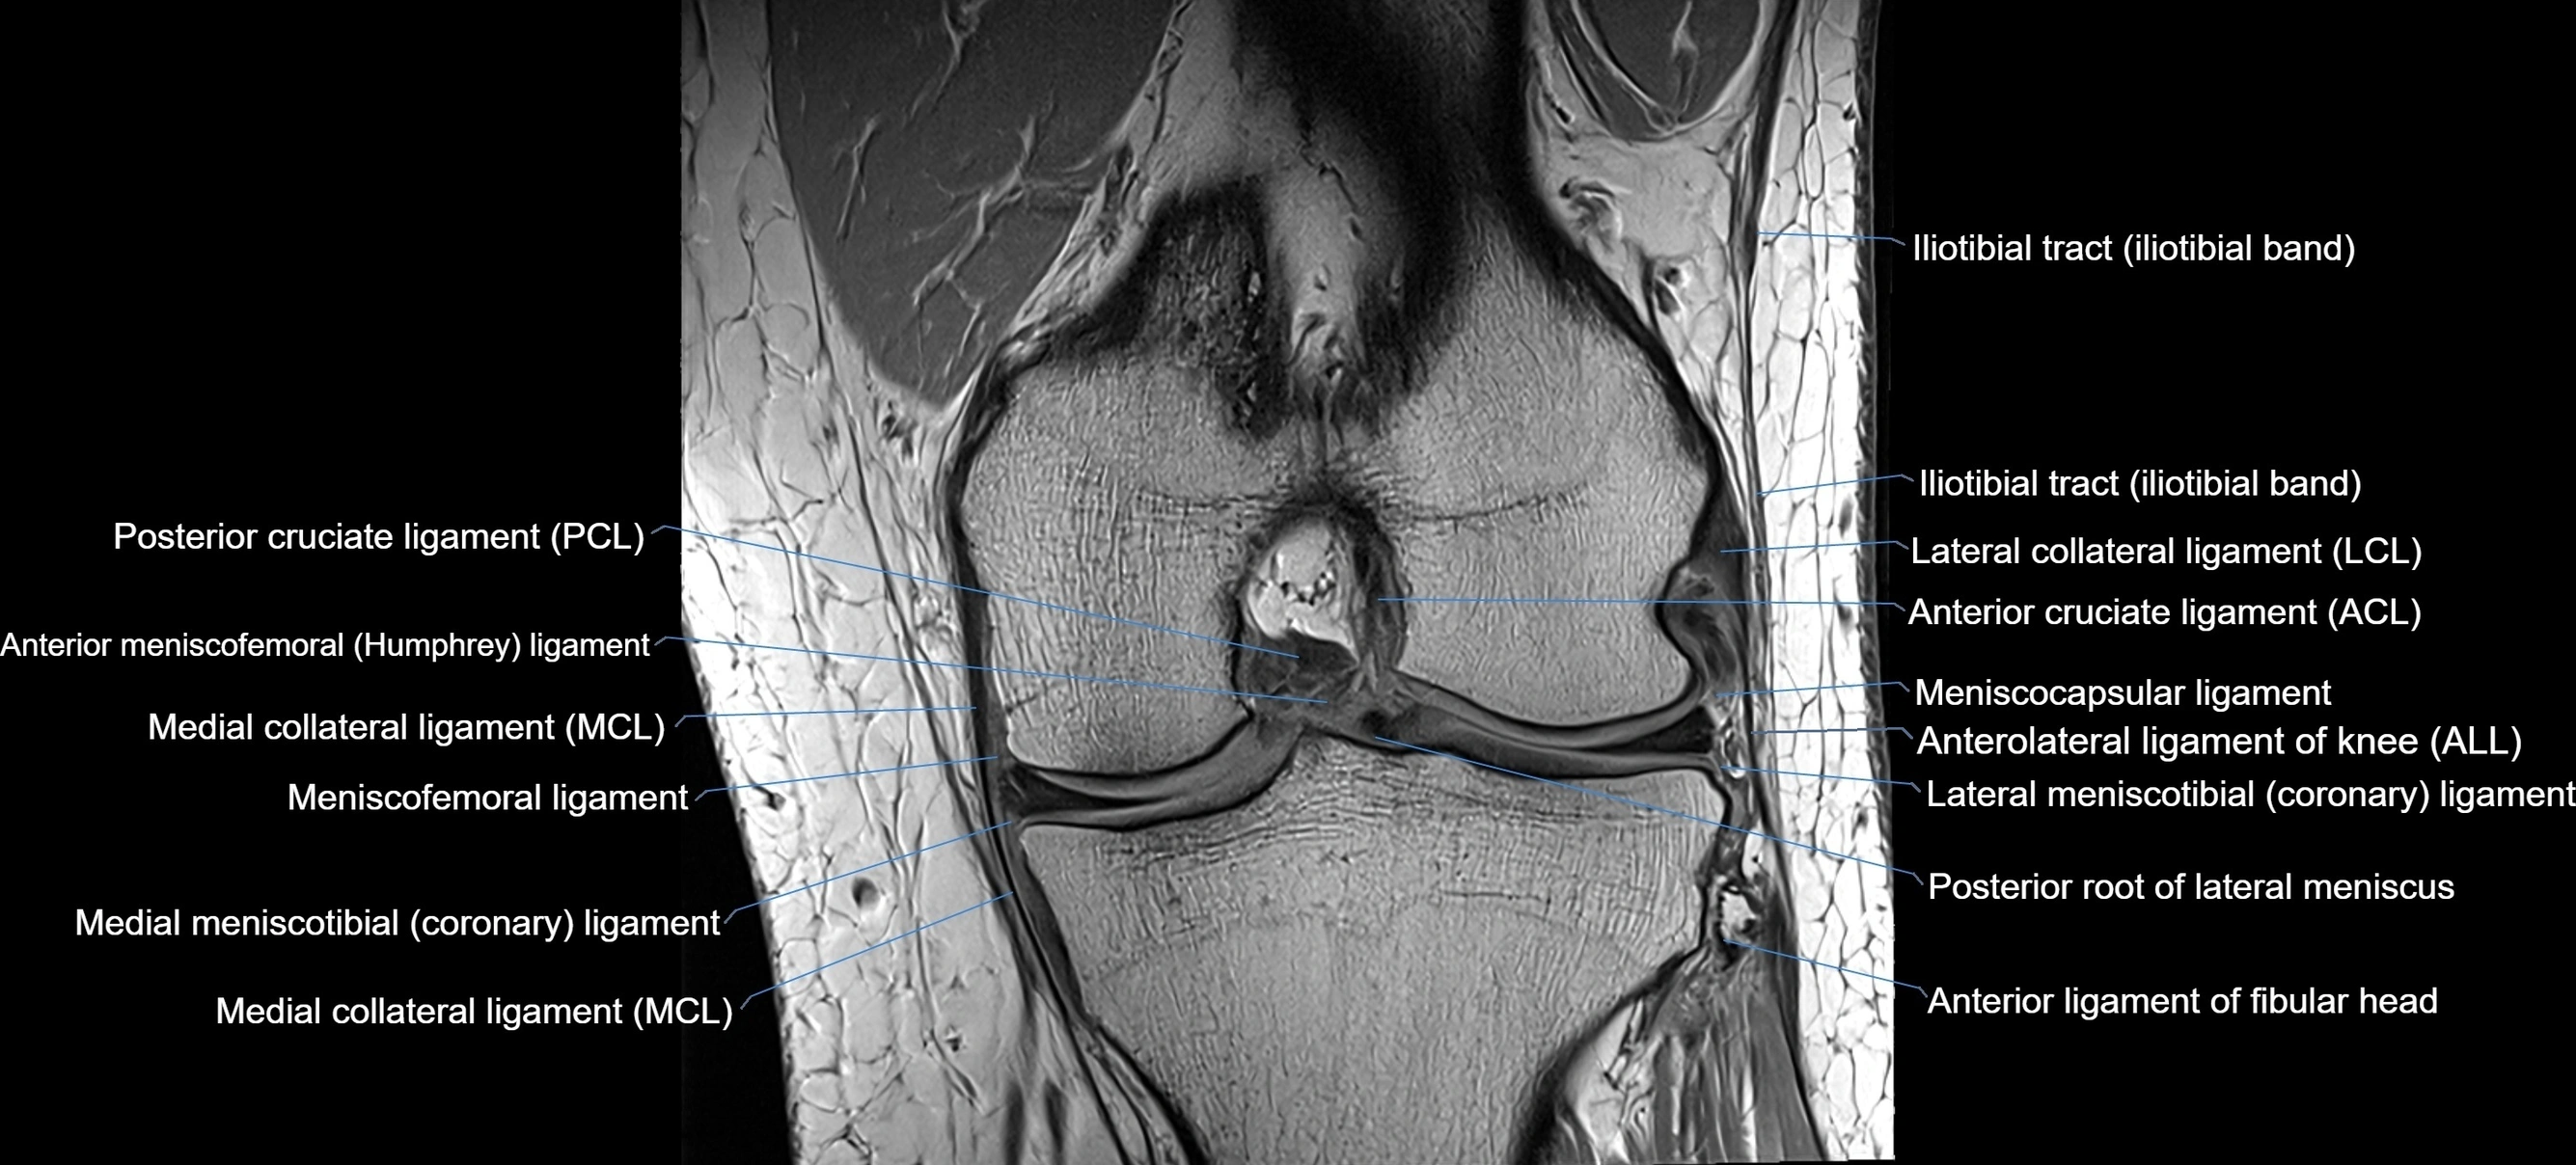

MRI images

image